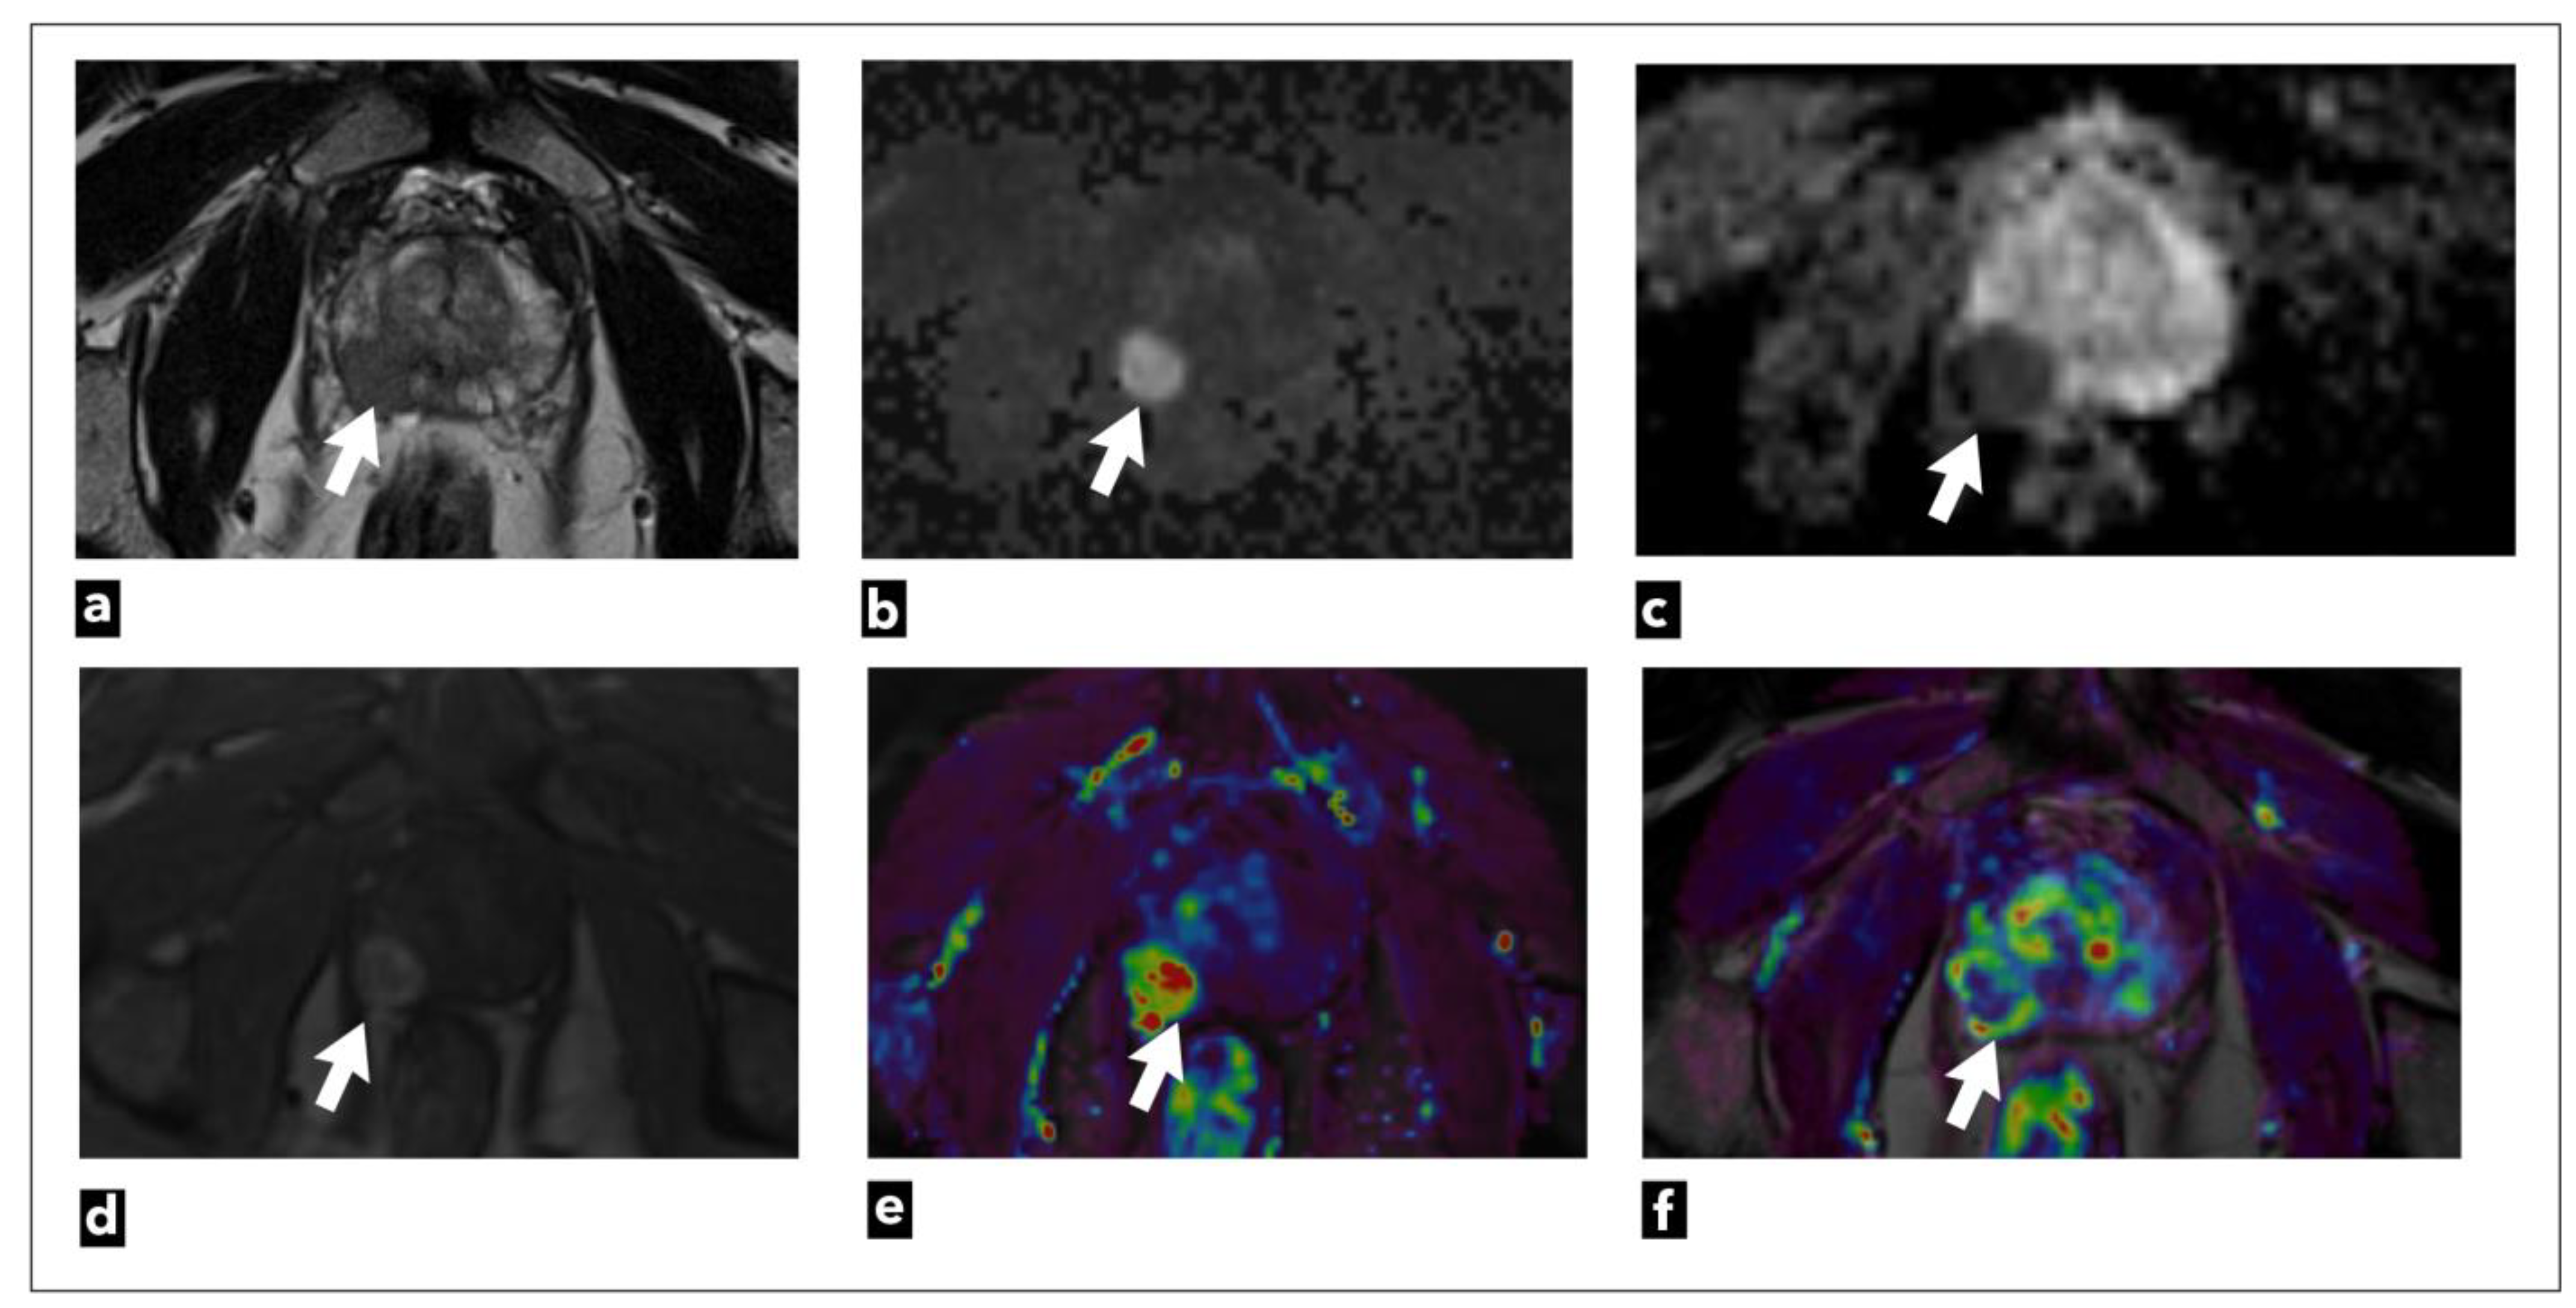

There are three analytic approaches to DCE-MRI analysis: qualitative, semi-quantitative, or quantitative [47]. Also, it can be analysed from raw data or using coloured parametric maps (Figure 2).

The currently valid PI-RADS v2.1 categorisation includes qualitative visual analysis, the simplest method of analysis, since it does not require special software, but can be analysed using a simple Picture Archiving and Communication System (PACS) workstation. This method relies only on the visual assessment of early arterial contrast accumulation in lesions previously observed as suspicious on T2W and DWI sequences. If early contrast accumulation is observed, the DCE-MRI finding is considered positive. However, DCE-MRI is considered negative [13] if early contrast accumulation is not observed or if diffuse contrast accumulation that does not correspond to the location of the T2W/DWI suspicious lesion is observed. The disadvantage of this method is the lack of standardisation and objectivity since interpretation is based on subjective assessment [47].

The second analytic method is a semi-quantitative method that analyses the kinetics of contrast accumulation on the observed lesion, wash-in, i.e., the arrival of the contrast agent in the lesion, wash-out, time to peak (TTP), and peak enhancement (PE) [48]. Using special software, the signal-intensity time curves are created [47]. There are three types of curves: type 1 curve (progressive) is a persistent curve in which there is a gradual increase in contrast accumulation and it is characteristic of benign changes; type 2 curve (plateau) is a curve in which there is an early and sudden contrast accumulation followed by a plateau; it can be seen in both benign and malignant focal lesions; and type 3 curve (wash-in and wash-out), a curve where there is an early and sudden accumulation of contrast followed by wash-out of the contrast agent, and this type of curve indicates the presence of prostate cancer (Figure 3) [49].

Using kinetic curves is a visually simple and easy-to-use method of analysis, but the shape of the curve highly depends on the injection quality, which makes it less reproducible [37]. Also, motion artifacts that result from peristalsis or patient motion artifacts can result in misregistration between successive slices, which is seen as noise in the curves. Special software used for image post-processing enables automatic correction of motion artifacts [13]. Parameters obtained with this method can be displayed and analyzed as parametric coloured maps which are fused with the T2W sequence for easier anatomical orientation [50].

The parameters obtained using this method are Ktrans (constant of transendothelial transfer of contrast medium from intravascular space to extravascular extracellular space), Kep (constant of transendothelial transfer of contrast from extravascular extracellular space back to intravascular space), Vp (plasma volume in relation to total volume tissue), and Ve (tumour extravascular extracellular space volume) [2,53]. These parameters provide information about microvascular permeability in observed tissue [54]. The obtained parameter values can also be displayed and analysed as parametric coloured maps fused with the T2W sequence for easier anatomical orientation. Time-concentration curves can be generated with this method using special software.

The semi-quantitative method was used in PI-RADS v.1 [8], while the qualitative method of DCE analysis is used in currently valid PI-RADS v.2.1 [9,10]. In the PI-RADS categorisation DCE-MRI has a clear application only in peripheral zone lesions characterised on DWI as PI-RADS 3. If there is an early arterial contrast accumulation in the observed change, it is upgraded to the PI-RADS 4 category, and if there is no early contrast enhancement, the PI-RADS 3 category remains (Figure 4) [9,10].

PI-RR is a scoring system that estimates the probability of prostate cancer local recurrence following radiation therapy (RT) (Figure 5) or radical prostatectomy (RP) (Figure 6).